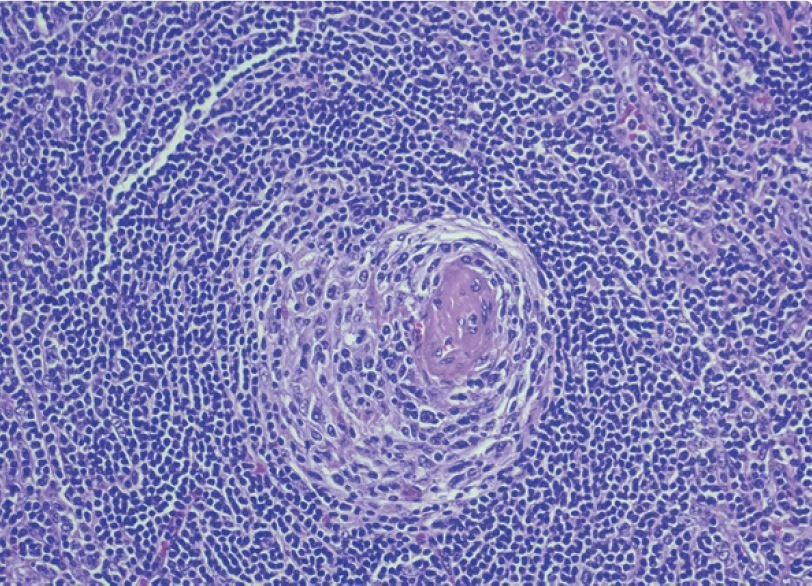

Zárodečné centrum s cibulovitým pláštěm (onion skinning). Foto iStock

K obecným histologickým znakům patří regresivní/atretická zárodečná centra s cibulovitými plášti (onion skinning), zdvojení zárodečných center (twinning), prominující sítě folikulárních dendritických buněk, interfolikulární proliferace postkapilárních venul s vysokým endotelem (high endothelial venules) a penetrace do zárodečného centra (lollipop sign), hyperplastická zárodečná centra a plachtovité interfolikulární infiltráty plazmocytů.